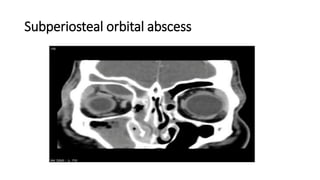

Subperiosteal orbital abscess

Preoperative assessment

• Physical examination confirms the

upper and lower eyelid retraction,

proptosis and other physical signs

of hyperthyroidism

• Complete ophthalmologic exam

• Complete head and neck exam

including thyroid status

• Ultrasound scan demonstrates

thickening of extraocular muscles

• CT scans of the orbit are essential,

should include PNS and rule out

any sinus disease.

• Thyroid profile